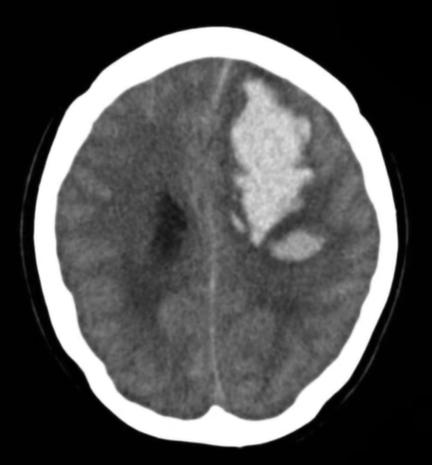

我迅速问了他的情况,心里隐隐觉得这并不是简单的头痛问题,很可能是急性脑出血或蛛网膜下腔出血。我立刻让他拨打120,赶紧120送往医院。30分钟后,我的手机上收到了家属传输的脑CT,果不其然,一看——颅脑脑叶出血!于是绿色通道抢救,迅速被推入手术室,经过脑外科医生清除脑血肿,算是挽救了生命,但目前留有引流管,还处于“昏迷状态”。

急性脑出血出血量至少80毫升,如果不及时手术,继续出血,后果不敢想象......。术后恢复究竟如何?目前未知?

本例额叶出血量接近100毫升,可能导致如下临床表现: